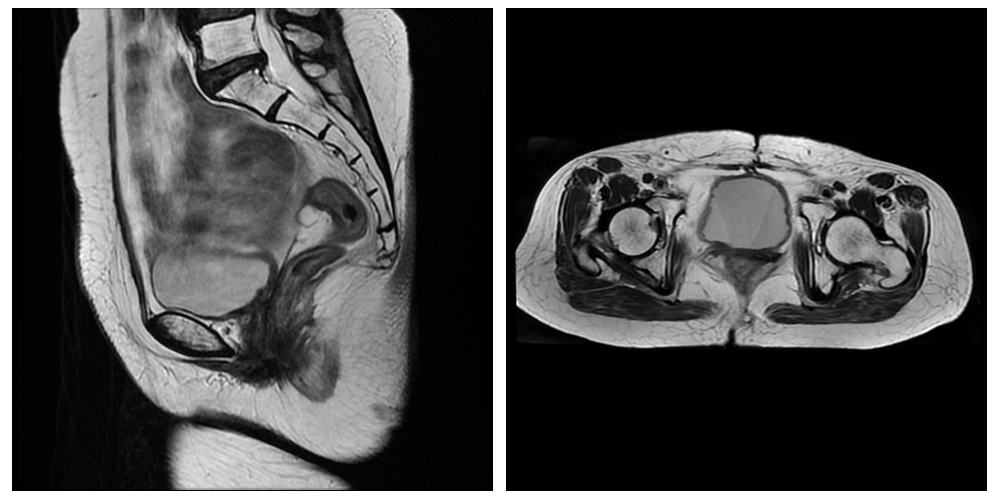

患者继续行4程原方案化疗后,于2022年3月至4月在我科门诊行宫颈癌根治性放疗(50Gy/25次),进一步巩固治疗效果。其后定期复查未见复发。2023年4月在我科复查盆腔增强磁共振,宫颈癌术后复查:未见明确肿瘤复发征象。目前患者病灶消失已持续1年半余,无任何不适症状。

复查盆腔增强磁共振:未见明确肿瘤复发征象